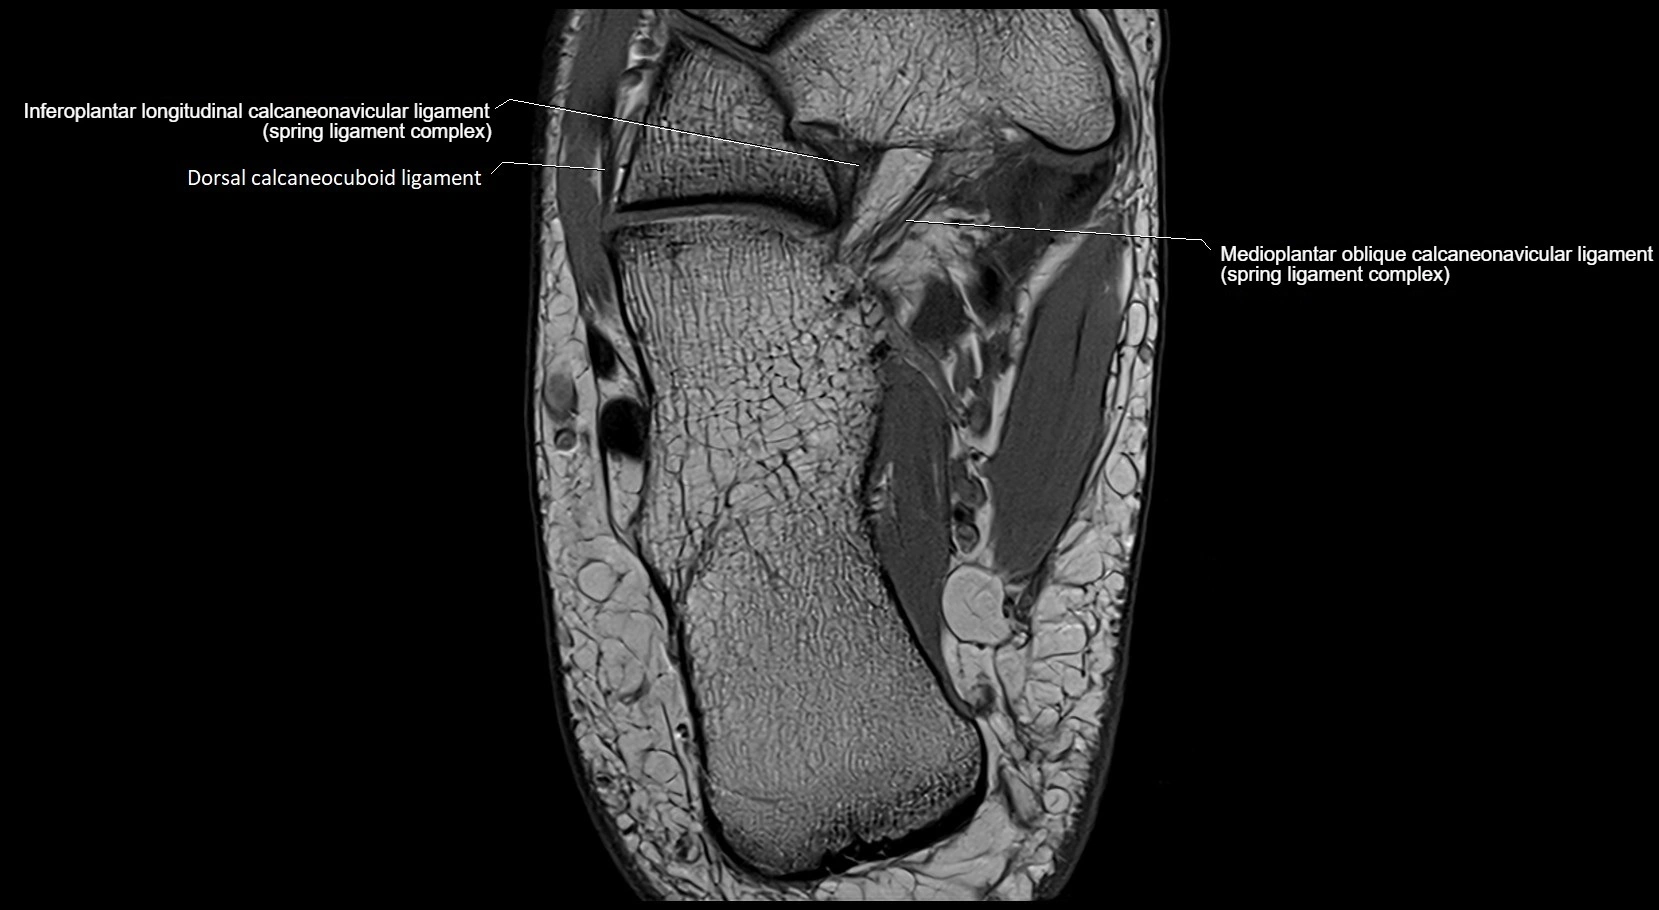

MRI image

image